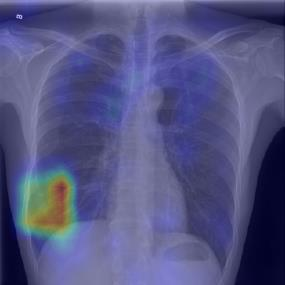

Chest X-ray (CXR) is the most typical diagnostic X-ray examination for screening various thoracic diseases. Automatically localizing lesions from CXR is promising for alleviating radiologists' reading burden. However, CXR datasets are often with massive image-level annotations and scarce lesion-level annotations, and more often, without annotations. Thus far, unifying different supervision granularities to develop thoracic disease detection algorithms has not been comprehensively addressed. In this paper, we present OXnet, the first deep omni-supervised thoracic disease detection network to our best knowledge that uses as much available supervision as possible for CXR diagnosis. We first introduce supervised learning via a one-stage detection model. Then, we inject a global classification head to the detection model and propose dual attention alignment to guide the global gradient to the local detection branch, which enables learning lesion detection from image-level annotations. We also impose intra-class compactness and inter-class separability with global prototype alignment to further enhance the global information learning. Moreover, we leverage a soft focal loss to distill the soft pseudo-labels of unlabeled data generated by a teacher model. Extensive experiments on a large-scale chest X-ray dataset show the proposed OXnet outperforms competitive methods with significant margins. Further, we investigate omni-supervision under various annotation granularities and corroborate OXnet is a promising choice to mitigate the plight of annotation shortage for medical image diagnosis.